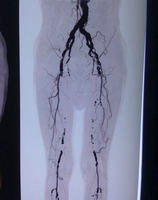

邹大爷转入血管外科后,郑州大学五附院血管外科专家王兵教授高度重视,当即指示主管医师王颖主治医师尽快完善下肢动脉CTA检查(图1),检查结果显示邹大爷双下肢动脉硬化闭塞症,双侧股浅动脉长段闭塞,同时左侧髂外动脉闭塞,缺血严重,导致截肢风险巨大,需尽早手术治疗。虽为双下肢病变,但目前患者左下肢症状突出,考虑到邹大爷年龄较大,合并多发基础疾病,同时手术治疗,手术时间长,麻醉风险大,与邹大爷家属沟通后拟先行处理左下肢病变。但不可规避的问题来了,邹大爷家处农村,经济条件很一般,如果按照理想状态去开通闭塞动脉,首选复合手术,即先行小切口取栓,将长段闭塞变为短段病变,而后行腔内治疗,狭窄或闭塞段行球囊扩张及支架置入,髂动脉及股动脉需分别置入支架,费用高达数万元。这笔费用对于这样一个家庭来说是远远不能承受的。但因为费用问题放弃治疗,邹大爷很快面临的就是截肢,甚至是生命危险!这样两难的境地也是外科医生经常面对的问题。最终,王兵教授凭借自己多年来深厚的外科功底,决定放弃腔内治疗,行传统的内膜剥脱手术,这样既能打通闭塞动脉,又可避免置入支架。同时考虑到邹大爷双侧股动脉闭塞,此次突发左下肢缺血症状,与髂动脉闭塞相关,所以本次手术以解决髂动脉闭塞为主,髂动脉打通后通过股深动脉的代偿,同样可以起到缓解症状的疗效。

图1